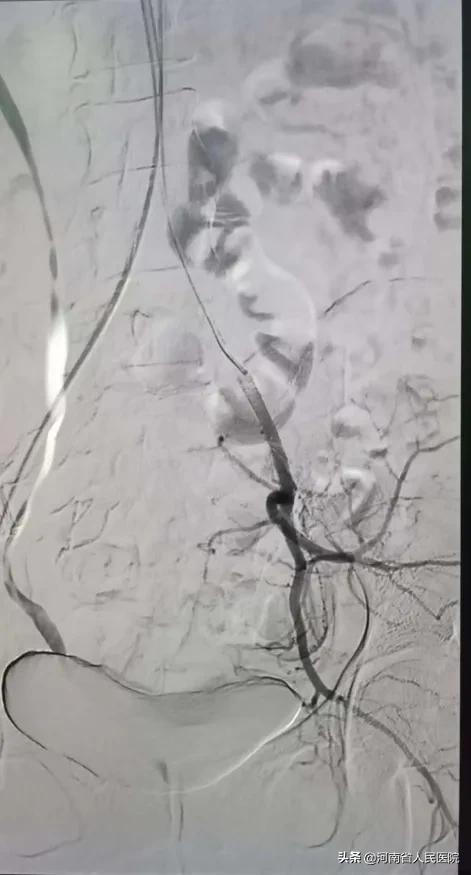

综合介入科主治医师刘建文带领刘玉岩医师,小心翼翼,利用导管、导丝巧妙配合,经过两个多小时的艰苦奋战,浑身衣服都湿透了,最终 成功将两侧血管栓塞 !

栓塞后子宫的供血动脉不再显影

随后,患者顺利接受了清宫手术。